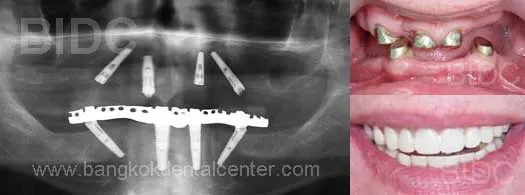

ตัวอย่างภาพของผู้ป่วยที่เข้ารับการปลูกรากเทียมด้วยระบบ All-on-4 ที่ศูนย์ทันตกรรม BIDC

คำวินิจฉัย: มีปัญหาการสลายตัวของกระดูกรองรับฟัน รวมทั้งสูญเสียฟันหลายซี่บนขากรรไกรบนและล่าง

วิธีการรักษา: รากเทียมระบบ All-on-4 พร้อมสะพานฟันบนขากรรไกรบนและล่างสามารถใช้งานได้ทันที และโดยไม่ต้องเข้ารับการปลูกกระดูก

ผู้ป่วยเดินทางมาจาก : ประเทศเนเธอร์แลนด์